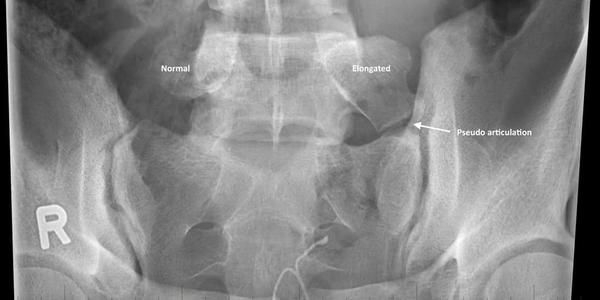

9. What abnormal spinal finding does this X-ray finding demonstrate?

Correct Answer: Bertolotti’s

Bertolotti's is a joint formed between the L5 TP and the sacrum, which can serve as a pain generator.